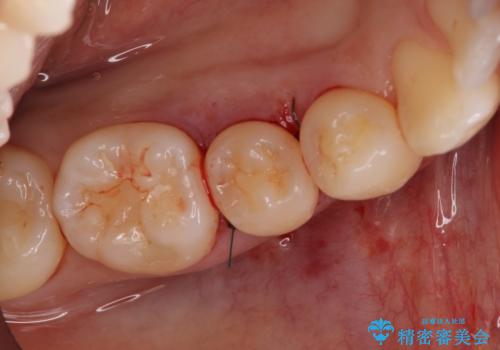

骨の再生治療手術をして10か月経過観察をしたのち、骨を平坦化する手術を行い、治療終了となりました。

・ほとんどの場合、2回目の手術(骨を平坦化する等)が必要になります。